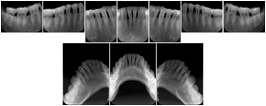

2. A patient requests cosmetic surgery to enhance their facial appearance. The case requires consultation between an orthodontist in New York and an oral surgeon in California. The cephalometric series of 2D projections constructed from a volumetric CT data set that is used for the discussion is arranged by a Structured Display for transfer between the two practitioners.

Cephalometric Series Structured Display

Figure OO-2. Cephalometric Series Structured Display